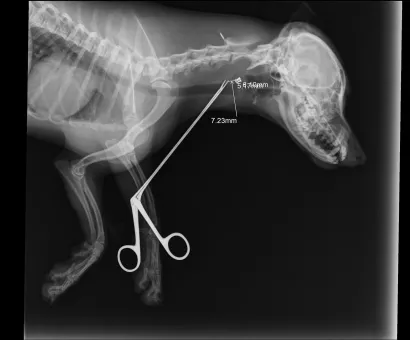

Maleni pas mješanac pogođen je dijabolom u vrat, a budući da je metak ostao smješten na nezgodnom mjestu blizu kralježnice, veterinar Mate Karaula iz Daruvara koji liječi Lenu, odustao je od vađenja metka zbog daljnjeg rizika po kujicu.

Prema nalazu veterinara dr. Mate Karaule, rendgenska snimka pokazala je da se metak, točnije dijabola, nalazi u području između atlasa i aksisa – dijela vratne kralježnice.

- Veličina projektila procijenjena je na 6,10 do 5,16 milimetara, a zbog dubine položaja i blizine kralježnice procijenjeno je da bi pokušaj vađenja mogao izazvati ozbiljne komplikacije. Zbog toga se odustalo od kirurškog vađenja metka.

Pas je primio injekcijsku sedaciju, obavljene su dvije rendgenske snimke i kirurška obrada rane, kazao nam je dr. Karaula.